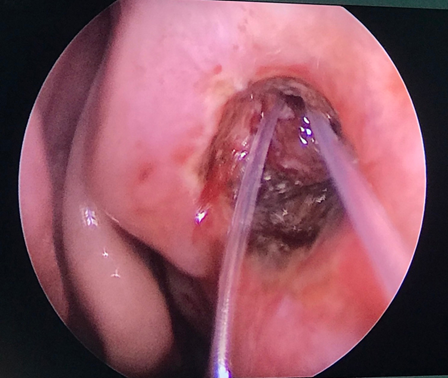

Vừa qua khoa Mắt - Bệnh viện Đa khoa tỉnh vừa tiếp nhận vầ điều trị Bệnh nhân nữ 49 tuổi vào viện vì xuất hiện khối sưng nề góc trong mắt trái kết hợp chảy mủ và chảy nước mắt nhiều. Tại đây bệnh nhân được xác định chẩn đoán Mắt trái: Viêm mủ túi lệ/ Tắc lệ đạo, bệnh nhân đã được điều trị nội khoa tích cực, triệu chứng lâm sàng giảm dần. Khoa Mắt và khoa Tai mũi họng đã kết hợp phẫu thuật cho bệnh nhân bằng phương pháp Nối thông túi lệ mũi bằng nội soi. Phẫu thuật này đã tạo đường thông trực tiếp từ túi lệ sang khoang mũi nhằm dẫn nước mắt từ mắt sang mũi. Sau phẫu thuật 2 ngày, các triệu chứng lâm sàng của bệnh nhân thuyên giảm và được ra viện sớm.

Hình 3. Ống Silicon được từ 2 lệ quản xuống mũi